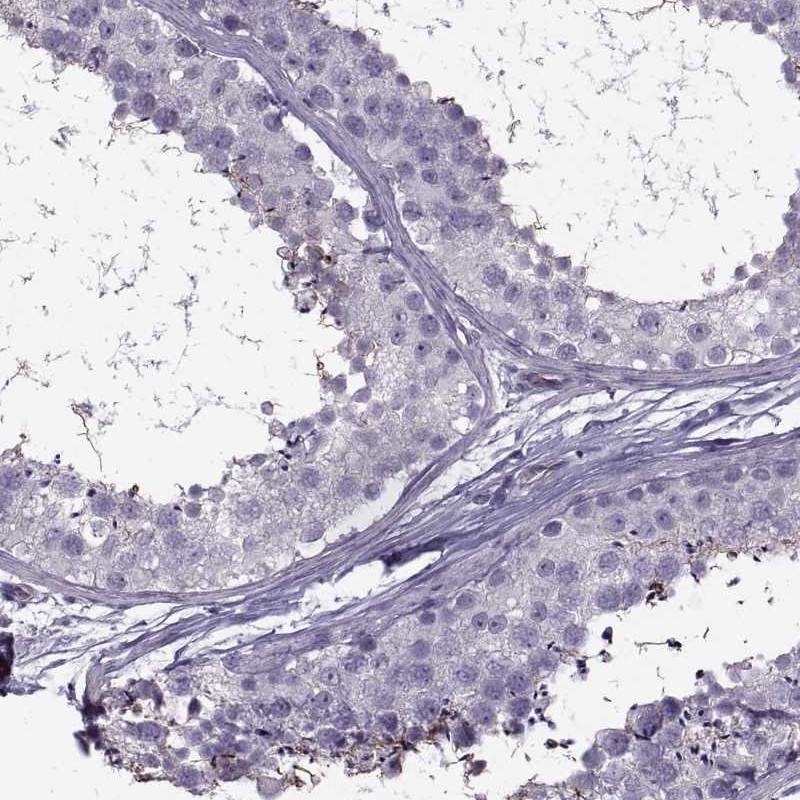

Immunohistochemistry analysis in human testis and endometrium tissues using Anti-ODF3 antibody. Corresponding ODF3 RNA-seq data are presented for the same tissues.